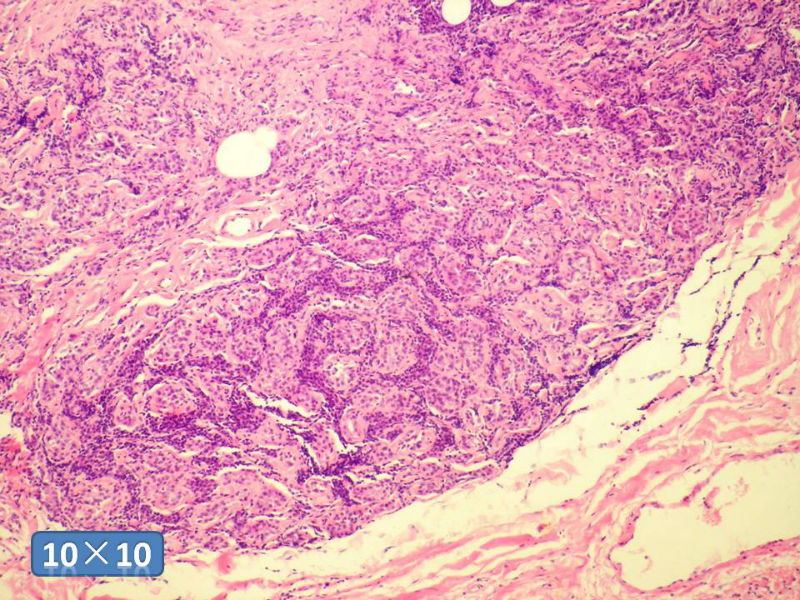

女性,50岁,乳腺肿物,冰冻切片(图1-25)

HE